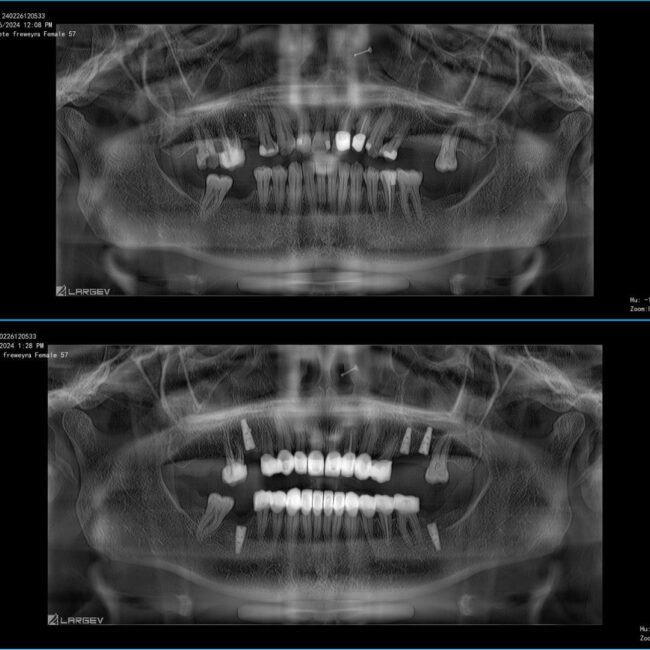

Jaw Cyst Treatment in Antalya: Key Symptoms, Potential Risks, and Surgical Procedures

Learn about jaw cyst treatment in Antalya, including symptoms, risks and surgical options. Discover how early diagnosis helps prevent complications and protects your oral health.